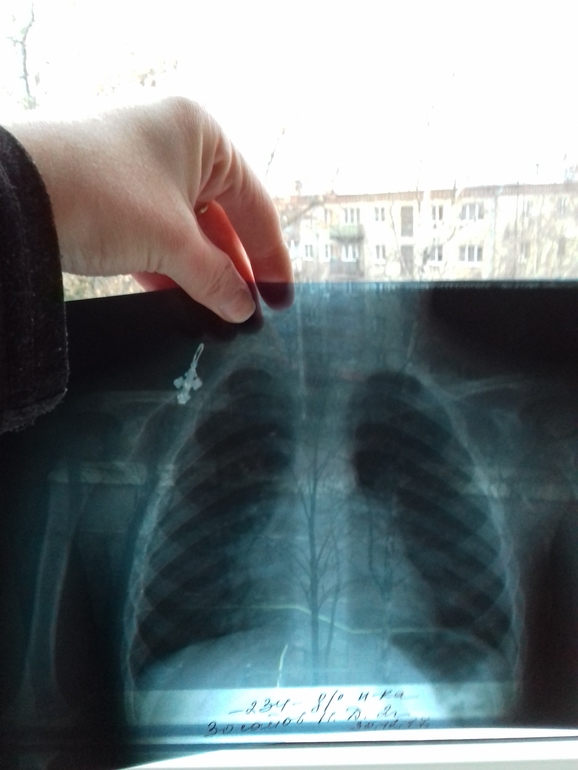

Долечились, я так понимаю...

Кровь, кстати, хорошая. Только соэ 16. Работает только рентген, врача, чтобы описать снимок, нет...

Вы прикалываетесь ))) такие снимки в живую то надо внимательно разглядывать, а уж на фоне окна и на фотографии вообще ничего не увидеть... более того, снимки надо смотреть в динамике, и лучше в 2х проекциях (детям конечно можно попробовать в одной, го как то я бы 2 сделала)...короче смысла его делать, если нет врача который посмотрит?

Если вы переживаете по поводу большого белого пятна на одном из легких,то зря.Нам 2 раза делали снимок и оба раза пятно было:1 раз бронхит,второй пневмония.Идите к врачу)

Все по -разному. У кого-то бронхит вирусный, у кого -то бактериальный. У вас какой?

Идите со снимком к платному. Не описАть, но поставить диагноз по снимку может и педиатр.